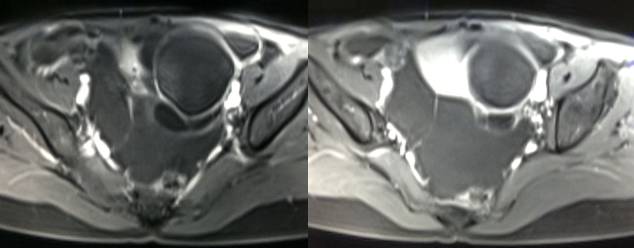

MR检查:

病理结果:黄体血肿

根据时间不同MR信号也有所不同,TIWI脂肪抑制序列可以鉴别脂肪和出血。

卵巢囊肿:呈均匀的T1WI 低信号,T2WI 高信号,边界清楚,壁薄,大多数病灶直径≤5 cm,但囊肿的起源及定性诊断困难。

功能性囊肿:因囊肿内容物成分不同,信号可有改变,随访观察数月后其信号和大小可出现变化或消失。

巧克力囊肿:常呈多发的单囊或多囊改变,病灶大小不等,囊壁厚薄不均,囊内信号复杂,囊内或各囊腔间血液因出血时期不同,信号常呈多样性,囊肿内反复出血、破裂,形成相互粘连的多房性囊肿,是其较为特征性的表现。

在鉴别卵巢畸胎瘤、出血性囊肿或巧克力囊肿时,MR 脂肪抑制T1WI 可明确肿块内高信号成分是脂肪还是出血,同时由于脂肪组织与非脂肪组织的共振频率不同,在两者交界处沿磁场频率编码方向出现化学位移伪影,但出血性囊肿与巧克力囊肿的鉴别有时较为困难。